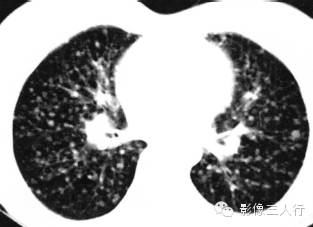

血行转移瘤为肺内多发结节影像,结节大小不等,可为多发大结节、1cm以下小结节或粟粒结节。结节随机分布,可位于胸膜下、支气管血管束周围及肺内。结节的密度均匀,骨肉瘤转移可有钙化。

报告书写:胸廓对称,双肺多发小结节影,大小,密度均匀。双侧肺门不大,纵隔居中,其内未见肿大的淋巴结。心脏大小正常,胸壁软组织未见异常(图1)。

图1血行转移瘤